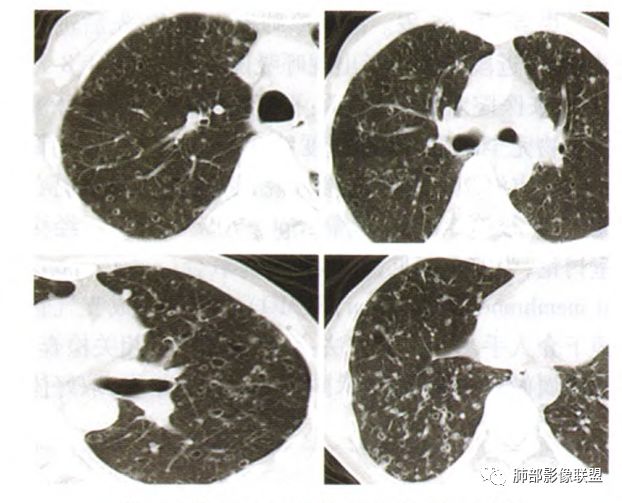

张延军:双肺多发结节,空洞影,后者洞壁厚薄不均匀,部分腔内丝丝落落,呈分叶征,边缘见毛刺影,病灶大部分位于胸膜下,与血管相连,右肺下叶前基底段结节近段支气管截断,远端见空腔。左肺下叶病灶密度不均,背段支气管壁增厚,管腔狭窄。考虑1.双肺下叶占位性病变伴肺内空洞性转移 2.多原发的占位 3.肉芽肿性血管炎代排。

背景是慢阻肺背景。病灶是多发结节伴空洞,内部见结节影,即空洞内结节,符合得有:GPA,癌,结核,真菌(隐球菌,曲霉)

初学者:也可以,壁结节,分叶

主要考虑在GPA和粘液性癌里面

无发热,其他慢性细菌先不考虑,有的低毒的,但是结节形态还是比较不规则的,分布也是比较随机,更像原发病灶。真菌方面,结节没有融合,坏死也是液化坏死,不符合隐球菌,曲霉不符合IPA,慢性吸入的也少见。结核没有树丫,不考虑。鉴别主要是GPA,和肺癌。GPA不支持点是皮肤,肾脏没有累及,ANCA不支持。。。肺癌主要是腺癌和鳞癌转移。比较支持的是淋巴结肿大,和左下肺的主病灶,支气管堵塞和异常强化。还有分叶,局部膨隆。可以建议支气管镜检测。

大家按我提的单个病灶分析,很多提出来都是典型的腺癌

脐凹征、粗短毛刺、深分叶、中央结构杂乱

本病例左肺下叶肿块,有深分叶、毛刺、胸膜牵拉凹陷、支气管截断及纵隔内淋巴结肿大等征象,都均支持病灶为恶性,如腺癌,而且叶间裂的多发结节也提示是腺癌来源可能大;双肺多发结节、肿块,大部分病灶有分叶、毛刺及胸膜凹陷的恶性征象,与原发肿瘤本身的性质有关,所以应该与左肺下叶肿块同源,而且双肺多发病灶内空洞也具有多样性;

此病例中空洞形态多样,内壁不光整,有分隔影,周围未见明显卫星灶及钙化灶,结核不太符合;患者病史慢性病史,无明显发热,缺乏中毒临床表现,急性感染基本排除;各种中性粒细胞胞浆抗体阴性,没有鼻窦炎,肾脏等病史,基本排除血管炎;霉菌性空洞常见于免疫机能低下者, 常为空洞、肺炎、伴“ 晕圈”征的结节及支气管扩张合并存在。